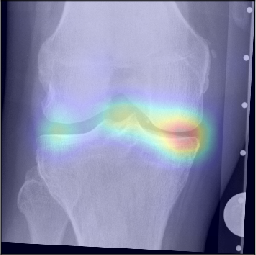

While machine learning-based approaches yield stronger prediction than conventional statistical models, (e.g. LR), they are less transparent, which can lead to lack of trust from clinicians. To address this drawback, various methods have been developed to explain the decisions of ”black-box systems” [24, 26, 27]. As such, we utilized the GradCAM approach [24] that allowed us generating an attention map, in order to highlight the zones where the CNN has paid its attention. While being attractive, this approach can also lead to wrong interpretations, i.e. there is no theoretical guarantee that the neural network identifies causal relationships between image features and the output variable. Therefore, a thorough analysis of the attention maps is required to assess the significance of certain features and anatomical zones picked-up by the model. Such analysis, however, could enable new possibilities for investigation of the visual features. For example, we observed interesting associations in the GradCAM-generated attention maps (Figure 5), some of which are not captured by KL grading. As such, tibial spines (previously associated with OA progression [28]) were highlighted in multiple attention maps. These associations, however, do not hold for all the progressors.

Figure 3: Examples of GradCAM-based attention maps for the knees progressed from no osteoarthritis to osteoarthritis. Fine-grained sub-types of progression are also specified. The presented images are of 140×140140140140\times 140 mm.